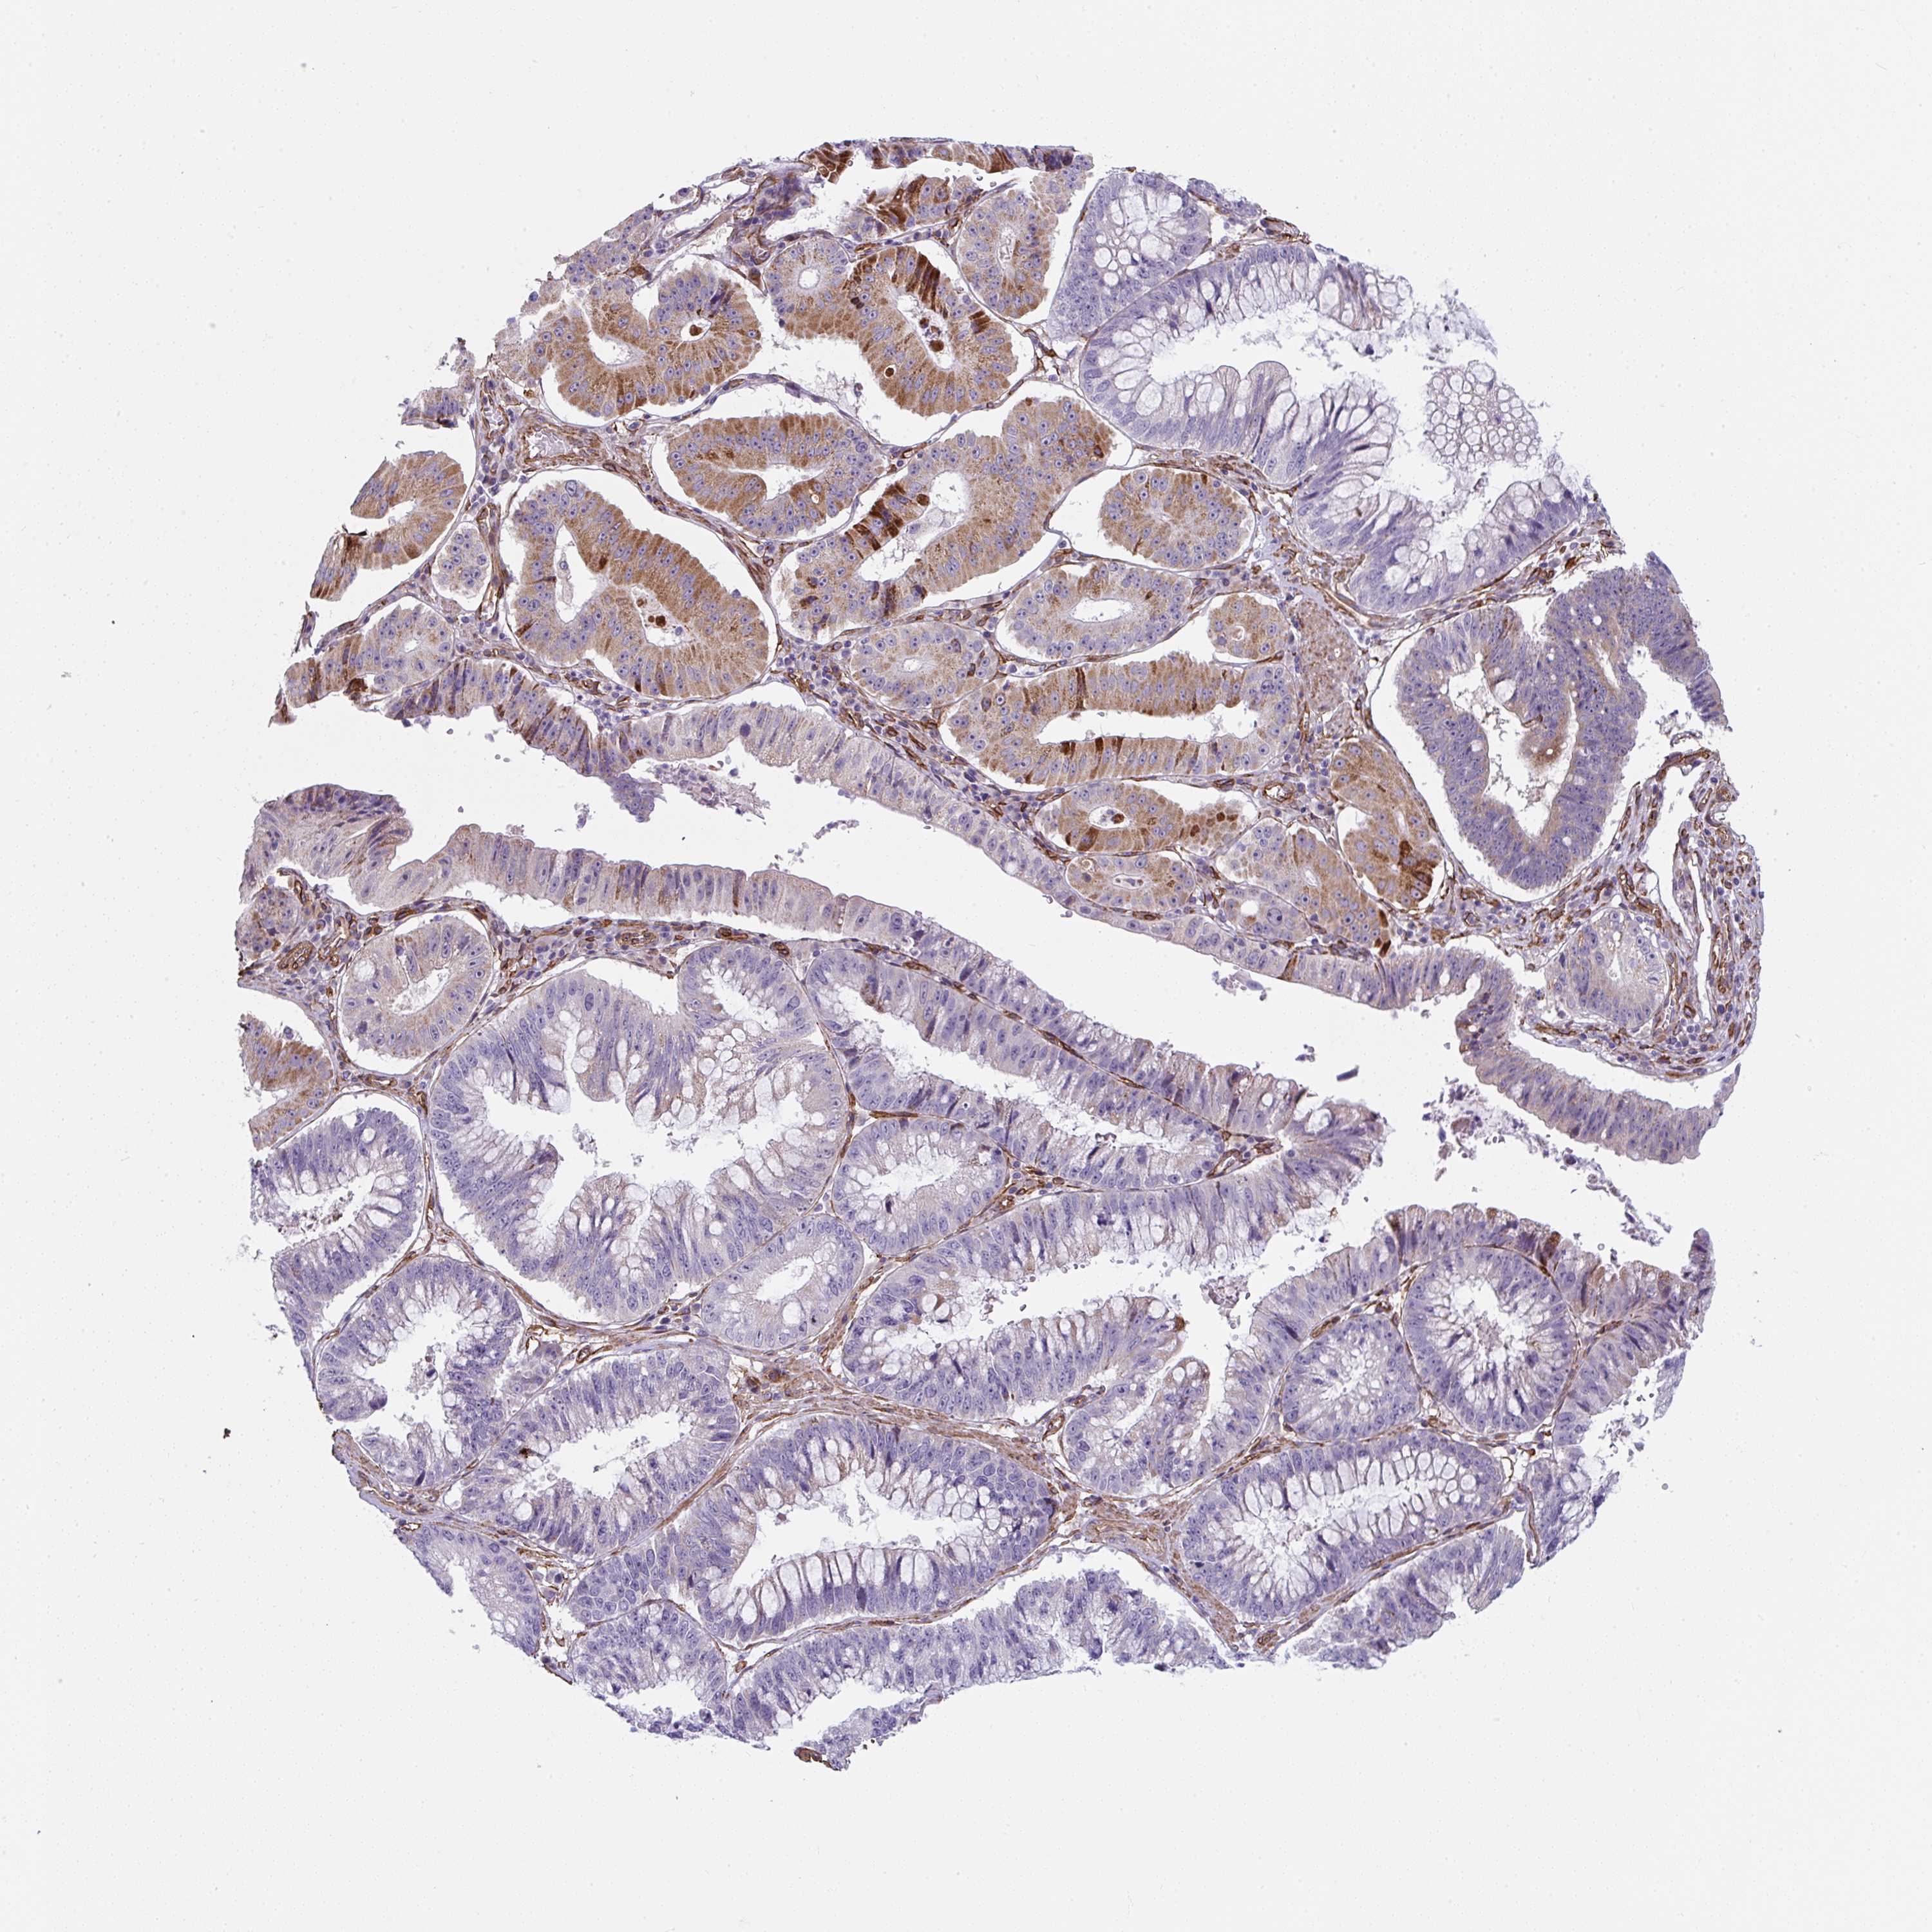

STOMACH CANCER - Protein expressioni

A mouse-over function shows sample information and annotation data. Click on an image to view it in a full screen mode. Samples can be filtered based on level of antibody staining by selecting one or several of the following categories: high, medium, low and not detected. The assay and annotation is described here.

Note that samples used for immunohistochemistry by the Human Protein Atlas do not correspond to samples in the TCGA dataset.

Antibody stainingi

Antibody staining in the annotated cell types in the current human tissue is reported as not detected, low, medium, or high, based on conventional immunohistochemistry profiling in selected tissues. This score is based on the combination of the staining intensity and fraction of stained cells.

Each image is clickable and will lead to virtual microscopy that enables deeper exploration of all samples and also displays staining intensity scores, fraction scores and subcellular localization as well as patient and tissue information for each sample.

Antibody HPA053749

Staining

High

Medium

Low

Not detected

Intensity

Strong

Moderate

Weak

Negative

Quantity

>75%

75%-25%

<25%

None

Location

Nuclear

Cytoplasmic/membranous

Cytoplasmic/membranous,nuclear

Adenocarcinoma, NOS